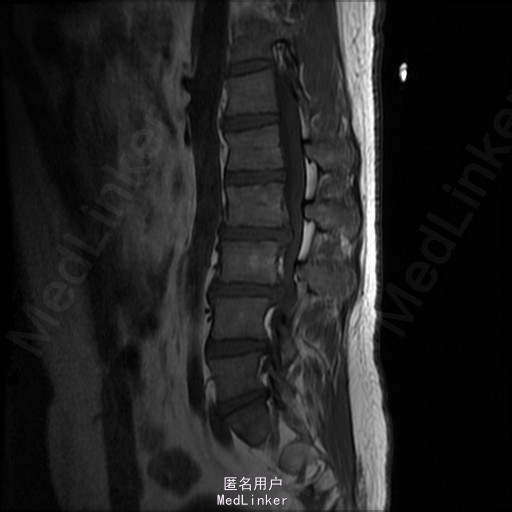

查体:腰部叩痛,腰部活动受限,左侧膝内侧、小腿外侧、内踝、足部感觉减退,右侧小腿、足背感觉减退,屈髋、伸膝、踝背伸肌肌力左侧4级,右侧4-5级,踇背伸、跖屈肌肌力左侧3-4级,右侧4级,双侧膝腱反射+,跟腱反射+,双侧巴氏征阴性,直腿抬高试验左侧40°阳性,右侧阴性。 辅助检查: X-ray:腰椎退行性变,多节段不稳 CT:腰椎间盘突出并椎管狭窄伴钙化,腰2-3,3-4,4-5,腰5骶1 MR:腰椎间盘突出并椎管狭窄,腰2-3,3-4,4-5,腰5骶1 上传受限无法全部上传,见谅

诊断:腰椎间盘突出症并椎管狭窄 处理: 1、完善相关辅助检查,明确诊断,有无手术指证; 2、完善手术评估,有无手术禁忌,手术风险及并发症; 3、在全麻下行腰椎后路多节段减压椎间植骨融合内固定术 4、腰2-3,腰3-4行开窗减压,腰4-5,腰5-骶1行椎间Cage植骨融合